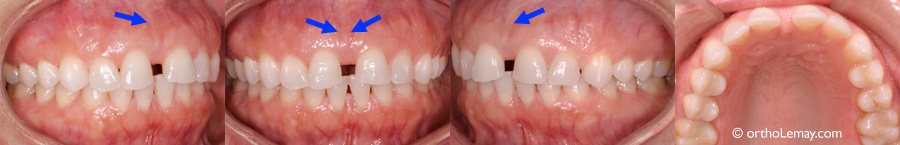

Autre exemple ou la simple éruption des canines supérieures (flèches rouges en C et D) a contribué à la fermeture d’un espace entre les incisives centrales (flèche bleue) et ce, sans qu’une frénectomie soit nécessaire.

Les canines suivent les racines des latérales dans leur parcours d’éruption normal et peuvent fermer l’espace entre les centrales sans aucune autre intervention. Il est préférable d’attendre la sortie des canines avant d’envisager une frénectomie labiale en présence d’un diastème. (Broadbent 1937)

Exemple de la fermeture d’un diastème entre des centrales supérieures suite à l’éruption des canines permanentes. (A) à l’âge de 8.9 ans, ce garçon présente un diastème important et un frein labial qui s’attache entre les centrales. (B) Près de 5 ans plus tard (13.5 ans) les canines permanentes sont sorties et ont contribué à fermer le diastème en déplaçant les incisives vers le centre. Aucune frénectomie n’a été faite.